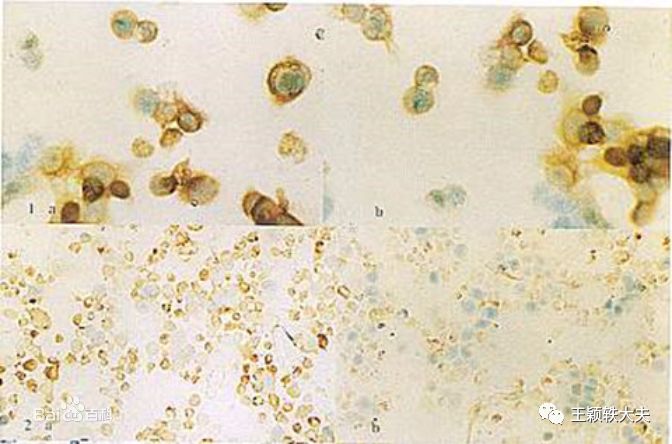

图片来源:网络

关于HPV感染的问题这几年国人非常关注,据2003-2004年来自美国的国家健康和营养研究课题的一个调查结果显示,14-59岁女性HPV总感染率为26.8%,HPV只感染人类,分为嗜皮肤型、嗜粘膜型等多种类型。

宫颈癌是全球女性中第4常见的癌症,每年约诊断530000例浸润性宫颈癌病例,每年约260000例宫颈癌死亡病例[15]。HPV与宫颈癌关联的证据有很多,几乎所有宫颈癌病例都可归因于HPV感染[16]。最常见的HPV类型为16、18、31、33、35、45、52和58型,HPV 16型占大约50%的病例,HPV 18型占大约20%。估计HPV 31、33、45、52和58型导致另外19%的病例[17]。